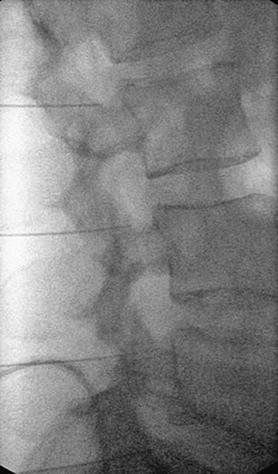

Τι είναι η διέγερση νευρικής ρίζας με εφαρμογή παλμικής ραδιοσυχνότητας

Πρόκειται για μια ελάχιστα επεμβατική πράξη, όπου μια ειδική βελόνα με ενσωματωμένο ηλεκτρόδιο εισάγεται στο σπονδυλικό τρήμα στο επίπεδο του ραχιαίου γαγγλίου της οπίσθιας ρίζας. με χρήση παλμικής ραδιοσυχνότητας γίνεται η διέγερση του γαγγλίου, με στόχο την τροποποίηση της μεταφοράς και αντίληψης των επώδυνων μηνυμάτων.